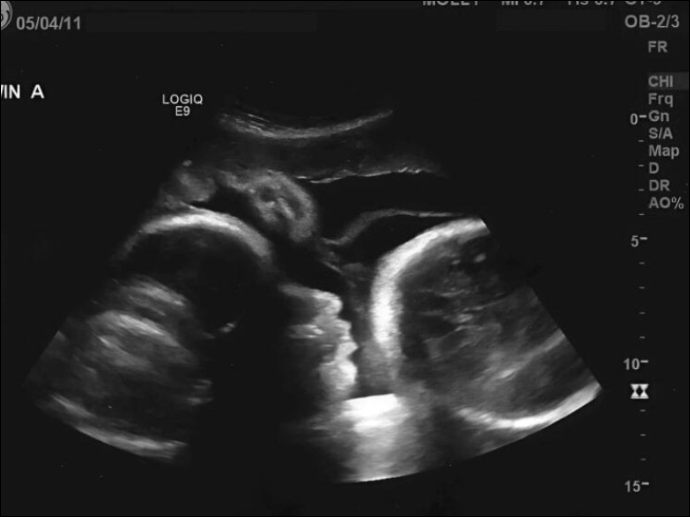

Larisa, elleriyle yüzünü kapatıp hıçkırıklara boğuldu. Gelecek olan bir bebeği beklerken, aslında kendi ölümünü beslediğini anlamanın ağırlığı altında ezildi. Mucizelere inanmak istemiş ama gerçeği aramaktan kaçtığı için en kıymetli aylarını kaybetmişti. Şimdi ördüğü o küçük patiklere bakarken, hiç var olmayan bir bebek için değil, elinden kayıp giden kendi hayatı için gözyaşı döküyordu.